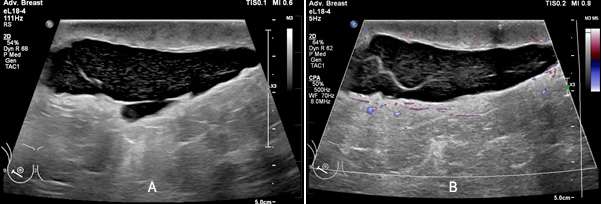

On ultrasound, seromas will present as a fluid-filled collection, which is well-circumscribed and anechoic or hypoechoic in echogenicity. The fluid within the seroma may be simple in appearance or mildly complex, often exhibiting posterior acoustic enhancement. When direct pressure is applied with the ultrasound probe during imaging, the seroma may compress, causing a change in shape or size.